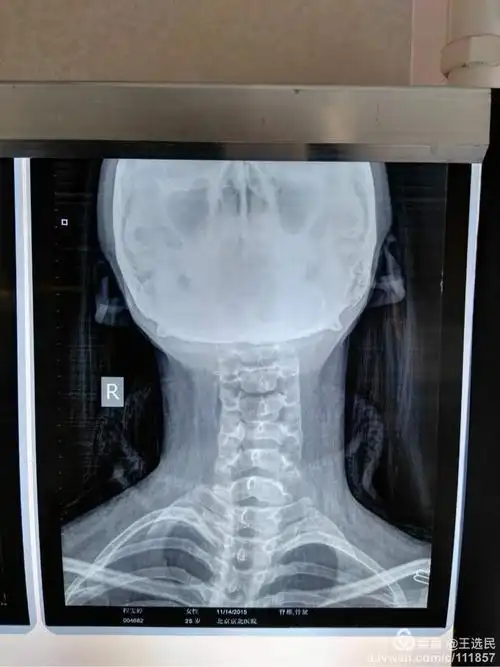

颈椎骨折脱位

完整颈椎正位,开口看到枕骨大孔和双侧枕骨髁,颞骨乳突,完整的枢椎齿

经过拍片检查,盈盈的颈椎第一,二,三椎向前错位.

他的颈椎x光照片,显示颈椎骨质轻度增生,但椎节稳定,无发育性椎管狭窄